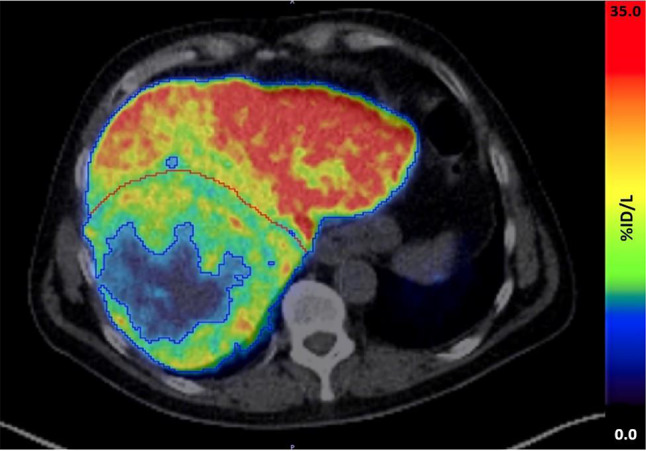

18F-FDGal PET/CT评价局部治疗对肝癌代谢性肝功能的影响。

Evaluation of the effect of locoregional treatment on metabolic liver function in hepatocellular carcinoma using <sup>18</sup>F-FDGal PET/CT.